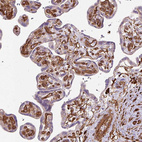

Immunohistochemistry analysis in human placenta and skeletal muscle tissues using HPA051237 antibody. Corresponding CNN3 RNA-seq data are presented for the same tissues.